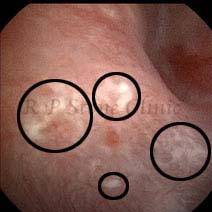

Kidney stone is a solid mass of CRYSTALS. It is the process of crystallization which initiates the formation of kidney stones. This happens in nephrons or units of kidney. Once a small crystal is formed, it can both grow & unite with other crystals leading to the formation of small concretion which eventually forms a stone. Once these large crystals detach from the collecting ducts, the process of stone formation starts in the renal collecting system. A recurrent kidney stone former is advised to know a little bit about something known as Randall’s plaque. Alexander Randall discovered plaques on the renal papillae eight decades back based on examination of 1154 pairs of autopsied Kidneys. He described these renal papillary lesions as cream colored or milk patch areas composed of calcium phosphate & calcium carbonate. These plaques could act as NIDUS for formation of KIDNEY STONE. Calcium Oxalate stone can form on this nidus & then detaches from this plaque to become a free floating stone in the collecting system of kidney

These images are taken as snap shots from the video recording of RIRS Surgery done at our hospital. These are Randall’s Plaques seen with Digital FLEX XC & Digital FLEX XC S. The cream or whitish patches are seen on the tips of RENAL PAPILLAE as seen in images below.

Randall’s Plaques may lead to the formation of Stones.

Those kidney stone patients who have Randall’s Plaques in their kidneys are more likely to form stones again (Recurrent Stones).

Stone Patients in whom Randall’s Plaques are detected at the time of RIRS Surgery should undergo regular ultrasound examination for early detection of stones.

Patients of Stones with Randall’s Plaques in their Kidneys should drink plenty of fluids in addition to Orange Juice & Lemonade.